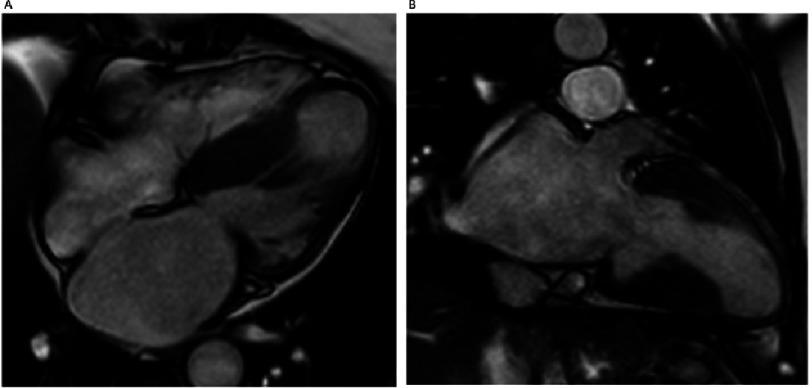

Clinical presentations of hypertrophic cardiomyopathy and implications for therapy.

Glob Cardiol Sci Pract. 2018 Aug 12;2018(3):19. doi: 10.21542/gcsp.2018.19.